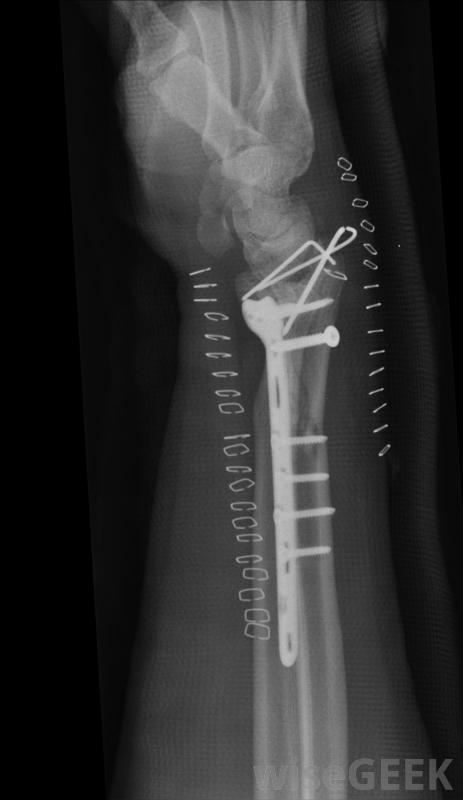

严重的撞击骨折通常需要使用钢板,用杆和螺钉将骨重新对齐。

当阻生骨折涉及大量骨碎片时,可能需要手术严重粉碎的骨头通常需要重建以避免进一步的损伤和正确的愈合。外科植入物,如金属螺丝钉、金属棒或金属针也可能被用来保持骨头的正确连接。手术后,受影响的区域可能需要一段时间的石膏或吊索,以限制活动,并使碎片重新团聚。

术后,受影响区域可能需要一段时间的石膏或吊索,以使骨碎片重新团聚。